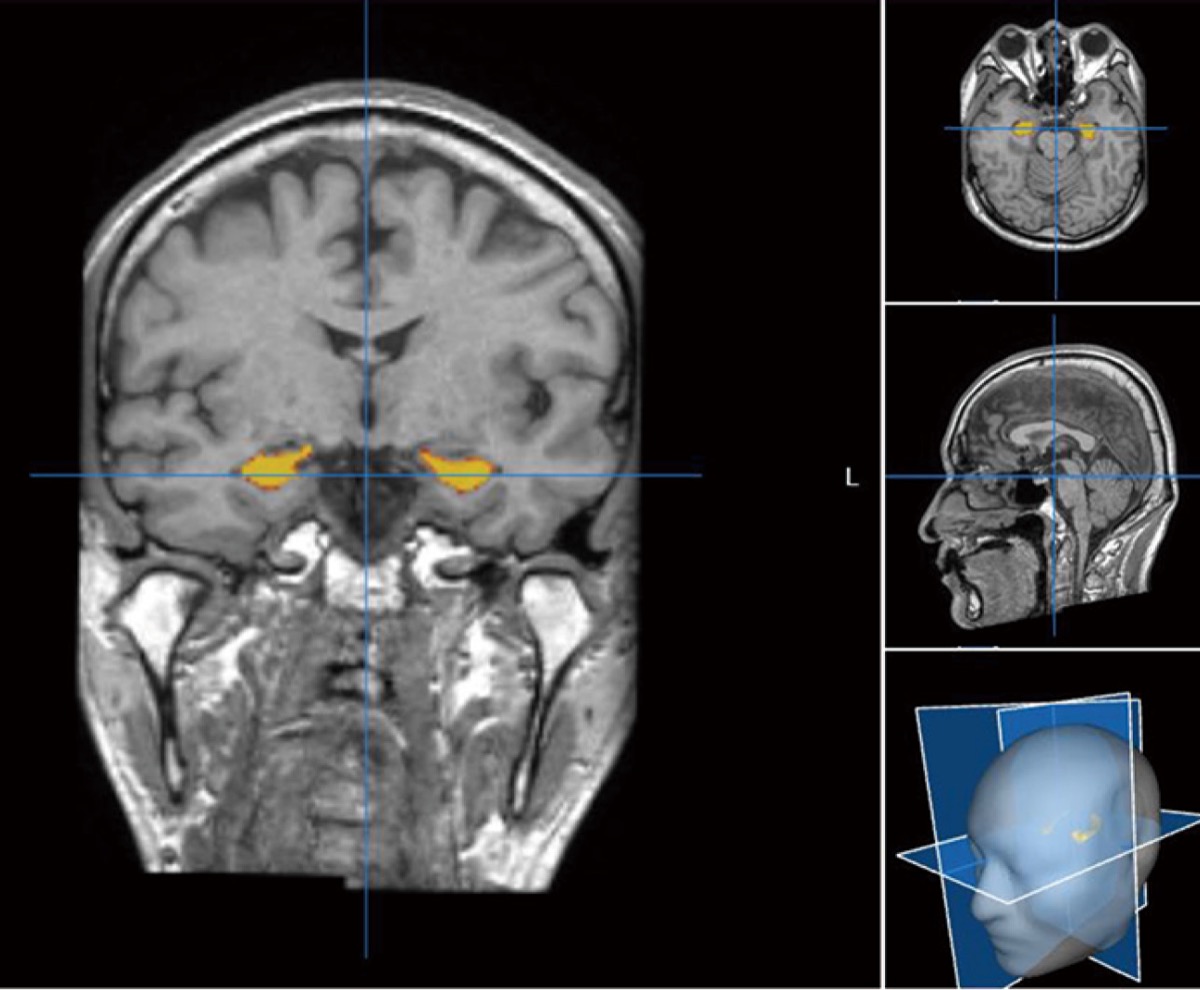

そこで眞鍋教授は、ADと密接な関係のある海馬の萎縮状態がわかるMRI検査に着目。MRI画像=写真=をAIでデータ解析することで、個々に応じた予防策を提案できるという。同病院では、次世代型のMRI画像診断「Brain SuiteR」を導入しており、これを用いた検査を行っている。